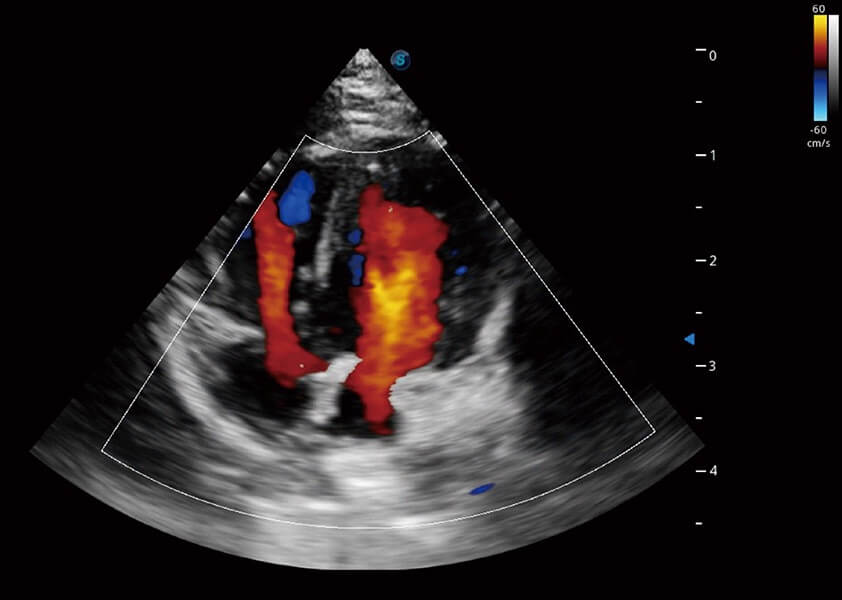

心臟解決方案

ProPet 60 配備了豐富的心臟探頭群、先進(jìn)的成像技術(shù)和專(zhuān)業(yè)的心臟測(cè)量工具,可幫助動(dòng)物醫(yī)生為不同體型和生理結(jié)構(gòu)的動(dòng)物提供心臟和心肌功能的全面評(píng)估。

(犬)四腔心血流